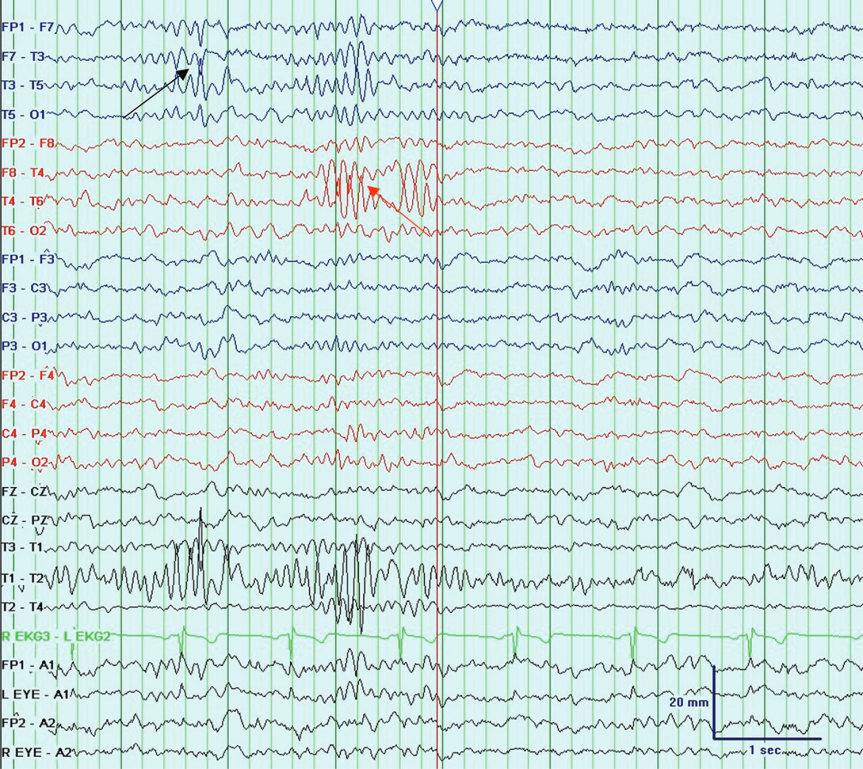

门柱波(Wicket Waves)

Wicket波因形似板球三柱门(Wicket)得名,表现为颞区(Temporal chains)的弓形Alpha活动(7-11 Hz),常以短串形式出现。

其核心特征包括:

无演变性:波形频率及形态恒定,不随时间改变。

无背景干扰:与癫痫样放电不同,Wicket波不伴后慢波或背景节律紊乱。

Wicket Waves